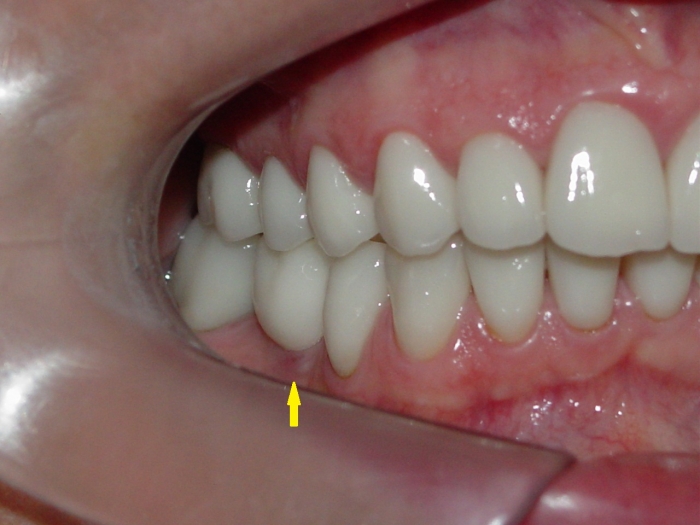

Imagens com facetas e prótese fixa em porcelana sobre implante

Sorriso inicial